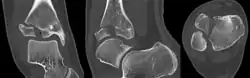

Same case on CT scan.

The fracture commonly results from an abduction-external rotation force, causing the anterior tibiofibular ligament to avulse the anterolateral corner of the distal tibial epiphysis resulting in a Salter Harris Type III fracture.